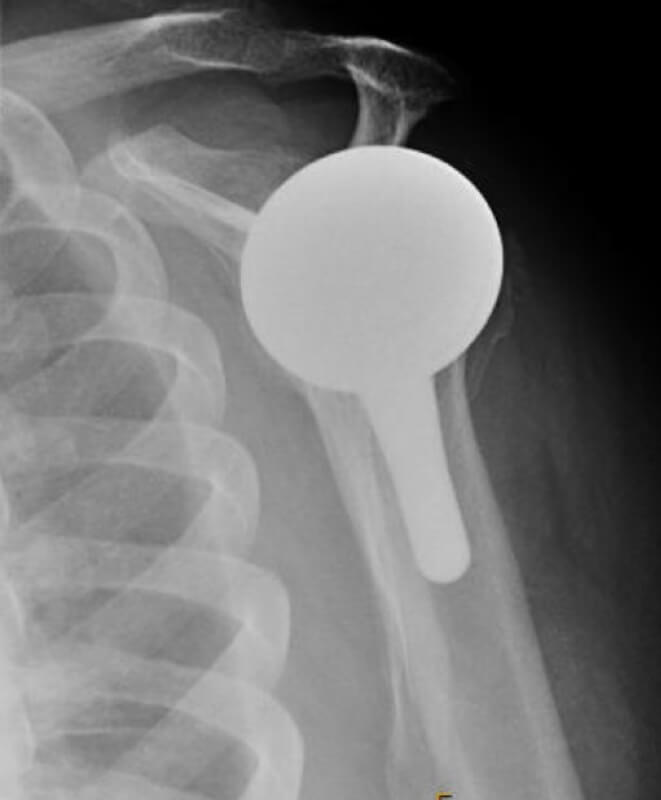

DJO/Enovis, Altivate